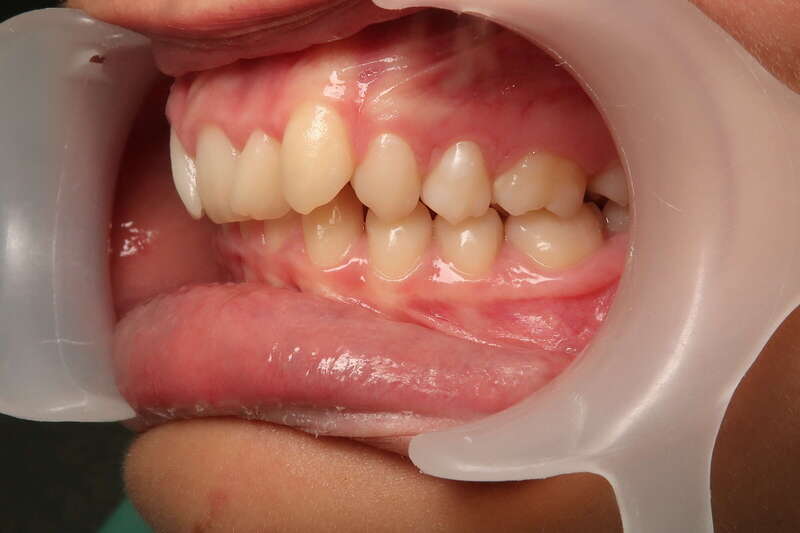

Cas n°3 traité par aligneurs (interception) - enfant

Intervenir dès 8 ans avec cette approche offre des bénéfices structurels :

• Symétrie Faciale : En éliminant le glissement de la mâchoire, on assure que le visage se développe de manière droite et harmonieuse.

• Confort Articulaire : Le recentrage prévient les tensions et les pathologies futures des articulations de la mâchoire (douleurs, craquements).

• Expérience Positive : L'absence de douleur et la simplicité des aligneurs favorisent une excellente acceptation du traitement par l'enfant.

• Simplification du futur : "Remettre la croissance sur les rails" permet souvent d'éviter des traitements beaucoup plus complexes (voire chirurgicaux) à l'adolescence.

Avant